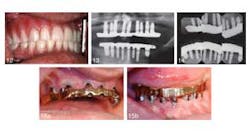

An article in the current issue of the Journal of Oral Implantology looks at long-term treatment for a patient with severe periodontal damage. The authors anticipate that the higher risk of implant failure in this patient will be offset by coating the implants with a rough, oxidized surface called TiUnite and by emphasizing the need for diligent oral hygiene. They also expect that by using overdenture prostheses instead of conventional removable dentures, they will improve stability and function — and thus patient satisfaction. Overall, increased use of implants has improved eating comfort and resulted in few complications after the surgery. However, pressure on implants is suspected to speed up loss of dense cortical bone in the jaw. Research has shown the TiUnite material stimulates bone growth, leading to faster fusion of implants and surrounding jawbone.RELATED | New material used in molar extraction sites optimizes bone regeneration and dental implant stability The current article is a case report on a 51-year-old patient who had been in a motorcycle accident and has a history of herpes, hepatitis, insulin-dependent diabetes, and persistent recurrent tooth decay. The patient’s remaining teeth (see photos below) were comprised of fractured crowns and older failing implants. The surgeons removed all of his teeth and old implants followed by the immediate insertions of new implants and stabilizing overdentures. Provisional implants were used for support during healing. Five months later, the interim provisional implants and prosthesis were removed and fabrication of a final restorative prosthesis was initiated.

RELATED | Atrophic patients have more options with new dental implant Despite the higher risk of implant failure due to his periodontal disease and diabetes, the patient’s implants have been in place for 12 years with no complications noted at routine checkups and cleanings. The patient has been instructed post surgery in proper use of floss threaders, deep-cleaning brushes, and an oral irrigator. His daily efforts to practice good oral hygiene improved his overall dental health. The patient was pleased with the results one week after the provisional implants were placed and was still happy with the surgery 12 years later. Little care and maintenance of the prostheses have been necessary.RELATED |Less invasive approach to dental implants allows heart patients to continue anticoagulation therapy The authors concluded that in this case the prostheses have been effective, predictable, and reliable. They contend that such positive results were only possible because the patient changed their at home oral care preventing plaque buildup and disease. Full text of the article “Twelve-year clinical and radiological results of a maxillary and mandible implant-retained bar overdentures carried out on oxidized (TiUnite) replace select implants: A clinical case,” Journal of Oral Implantology, Vol. 39, No. 6, 2013, is now available here. The Journal of Oral Implantology is the official publication of the American Academy of Implant Dentistry. For more information about the journal or society, please visit their website.